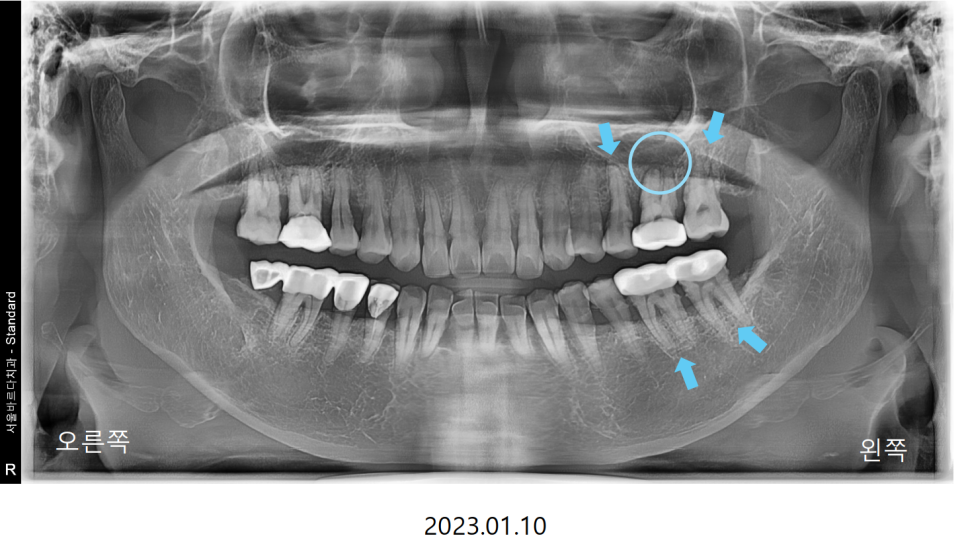

씹을때 먹먹하고 한쪽으로만 식사를 하신다는 이야기를 듣고

전반적으로 뼈와 치아 상태를 확인하는

파노라마 엑스레이를 촬영하여 보니

통증이 있다고 하는 왼쪽 위 큰어금니2개와

바로 그 앞의 작은어금니가 많이 흔들리는 상황이였습니다.

다수의 치아가 흔들리는 상황이였기에

치아의 뿌리를 조금 더 정밀하게 볼 수 있는

치근단 엑스레이와 CT를 추가적으로 촬영하였습니다.